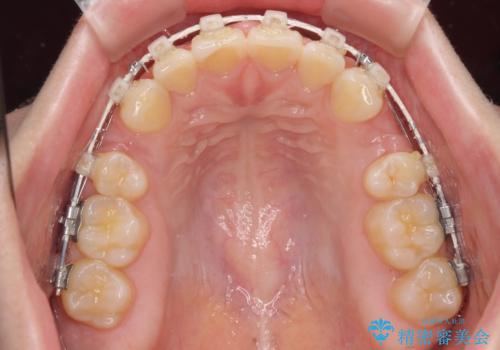

- 矯正装置

- 審美装置

- 出っ歯と口の閉じにくさ、デコボコを気にして来院された患者様です。

口元の突出感を改善するため、上下左右第一小臼歯4本の抜歯を行い、ワイヤー装置による矯正治療を行うこととしました。

抜歯矯正を行ったことで、顎先のつっぱり感や口元の閉じにくさを解消することができました。